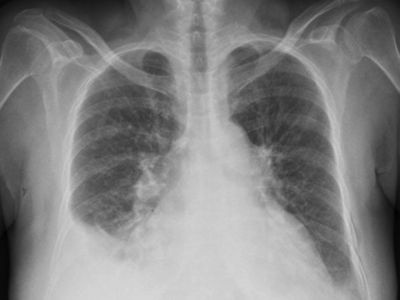

Cardiac Resynchronization Therapy (CRT) and an Implantable Cardioverter-Defibrillator (ICD) work together to support heart failure patients. CRT improves coordination between the heart’s chambers, helping the heart pump better, while an ICD prevents dangerous fast rhythms. You may need this treatment when-

Your heart’s pumping function is low